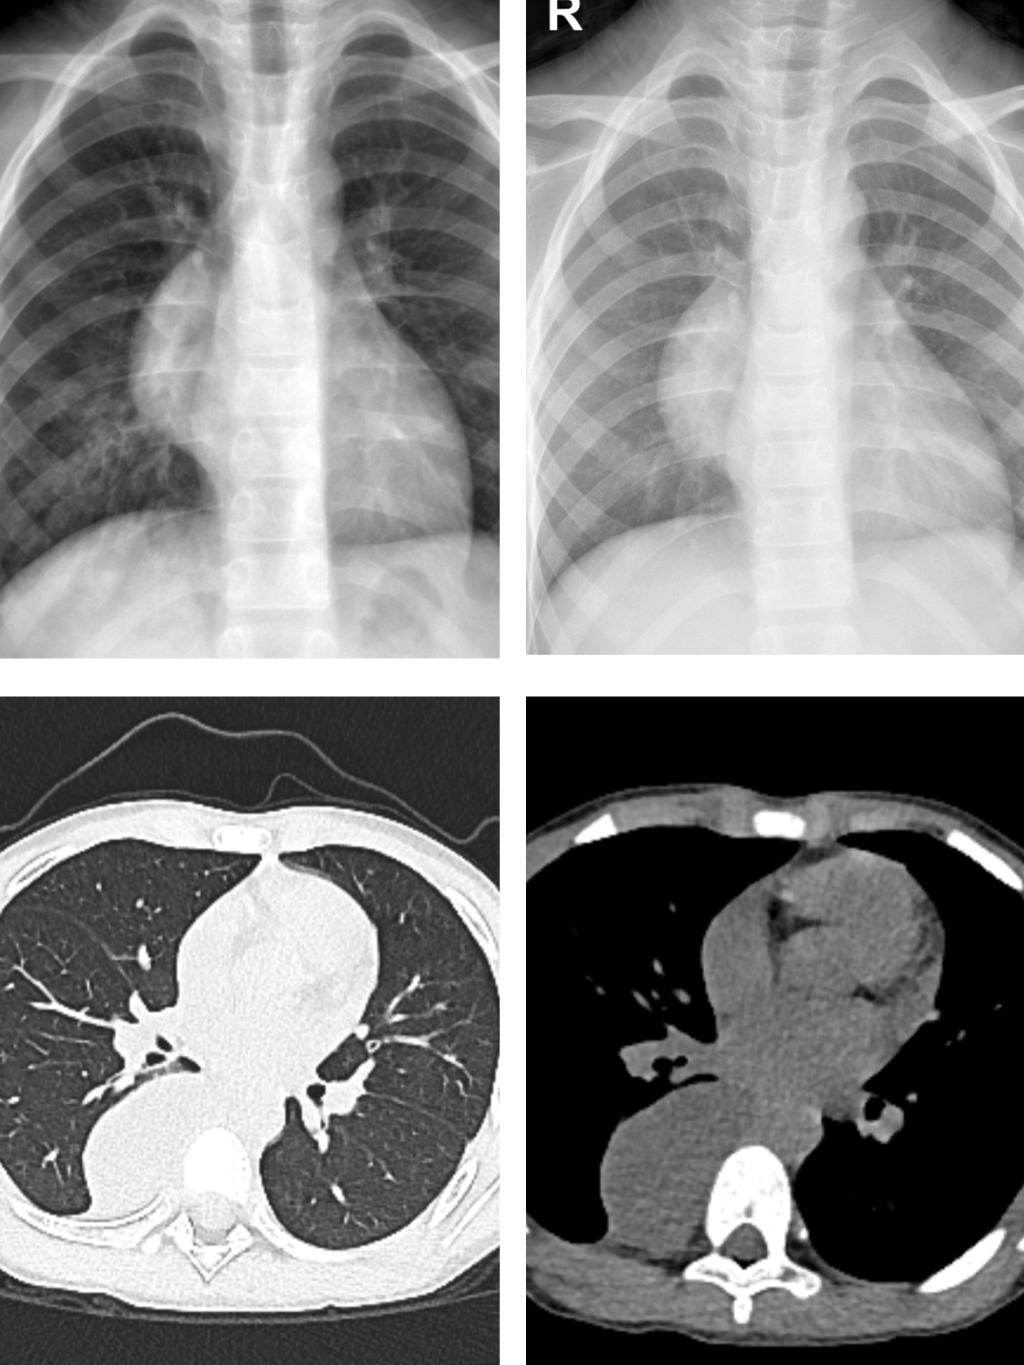

一直到1月18日,穆主任前后给家属打了六、七次电话劝说家属重视检查,最终孩子母亲拗不过穆主任,同意到医院做CT,结果显示孩子后纵膈、右侧椎体旁异常密度影,考虑为神经源性肿瘤可能性大。